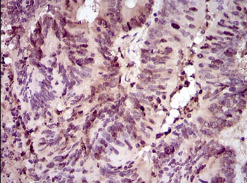

IHC    1/100 - 1/500